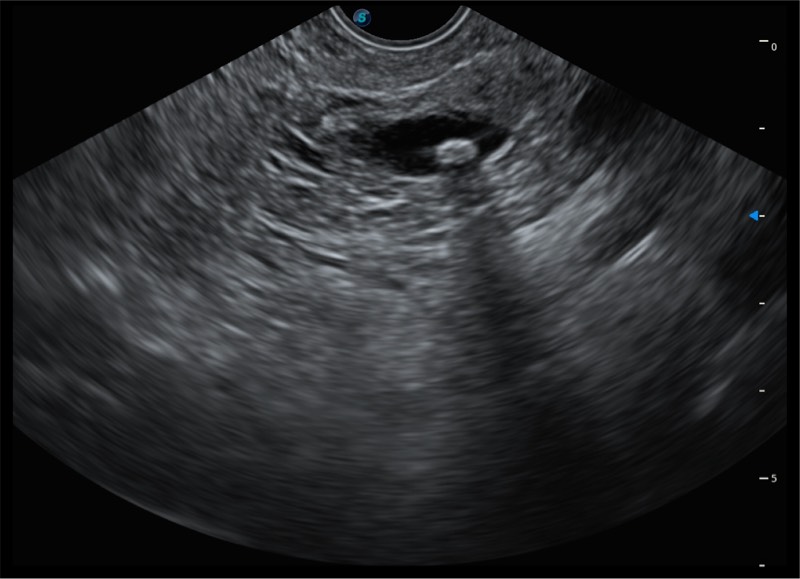

基于二十年的超声技术积累,乐玩lewin国际提供了最新一代的独立超声主机,在提供高质量图像的同时满足多学科使用。具备常见多普勒技术并提供弹性成像、声学造影等高端影像技术。新一代传感器具有更强的抗干扰能力并减少图像伪影。